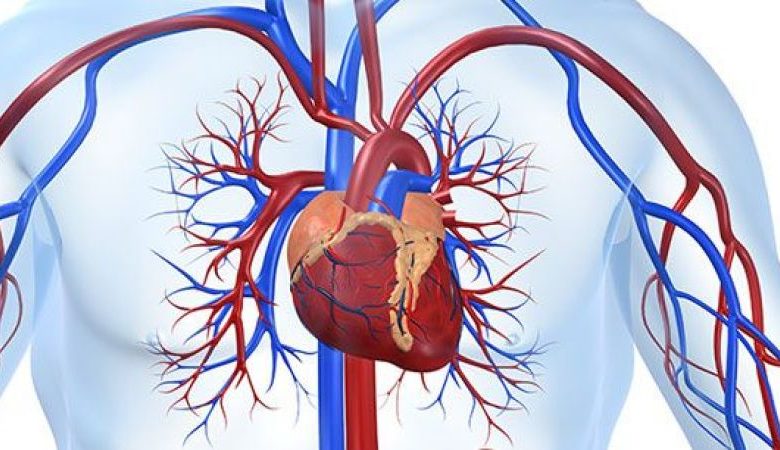

Kalp ve damar sağlığı, kardiyoloji adı verilen tıp dalı tarafından incelenen ve yönetilen bir alanı ifade eder. Kardiyoloji, kalp ve damar sistemine odaklanarak kalp hastalıkları ve damar sorunlarıyla ilgilenir. Bu tıp dalı, kalp hastalıklarının teşhisini, tedavisini ve önlenmesini içerir. Kardiyologlar, kalp ritmi bozuklukları, kalp krizi, kalp yetmezliği, yüksek tansiyon, damar tıkanıklıkları, anjina gibi bir dizi kalp ve damar hastalığının teşhisini koyarlar. Ayrıca, kalp sağlığını korumak için yaşam tarzı değişiklikleri, ilaçlar ve gerekirse cerrahi müdahaleler gibi tedavi yöntemlerini de uygularlar. Kardiyoloji, kalp ve damar sistemi ile ilgili her türlü sorunun tanı ve tedavisini gerçekleştiren önemli bir tıp dalıdır.